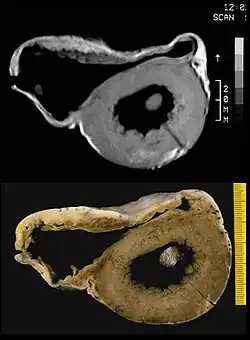

Biopsy

Transvenous biopsy of the right ventricle can be highly specific for ACM, but it has low sensitivity. False positives include other conditions with fatty infiltration of the ventricle, such as long-term excessive alcohol use and Duchenne or Becker muscular dystrophy.

False negatives are common, however, because the disease progresses typically from the epicardium to the endocardium (with the biopsy sample coming from the endocardium), and the segmental nature of the disease. Also, due to the paper-thin right ventricular free wall that is common in this disease process, most biopsy samples are taken from the ventricular septum, which is commonly not involved in the disease process.

A biopsy sample that is consistent with ACM would have > 3% fat, >40% fibrous tissue, and <45% myocytes.

A post mortem histological demonstration of full thickness substitution of the RV myocardium by fatty or fibro-fatty tissue is consistent with ACM.